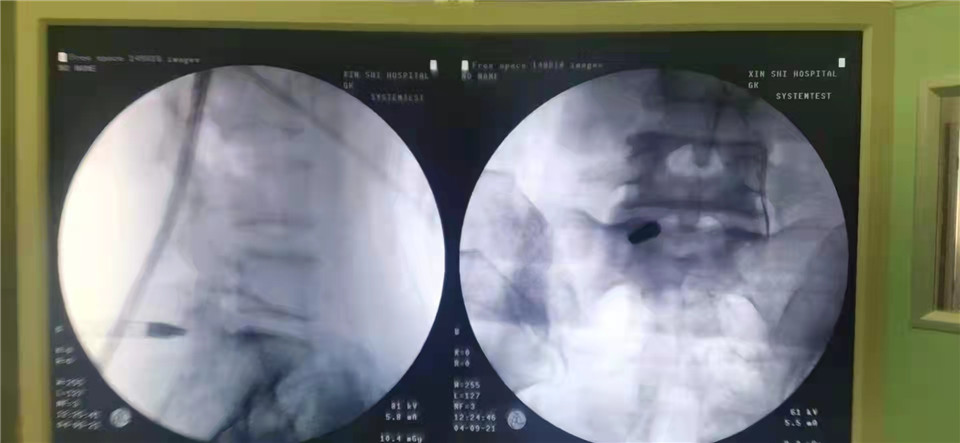

小拇指粗的内镜, 让患者轻松告别病痛折磨 接受治疗的这位女性,虽然才40出头的年纪,却长时间被腰腿放射性疼痛困扰着,以至于难以正常地生活和工作。就诊后,经过医生细致的检查,抓住了罪魁祸首——腰椎间盘突出。 “她下肢的疼痛,是神经被压迫导致的。”胡主任解释道:“她腰椎的最下面一节椎间盘突出很大,导致骶1神经根受到了很明显的压迫,已经被挤压得变形了。这些神经与下肢的感受密切相关,也就造成了现在的症状。”由于该患者的病情已经对生活造成了严重的影响,因此必须接受手术治疗。 为了解救被压迫的神经,胡主任拿出了科室的一项“法宝”:腰椎椎板间内镜技术,只需在患者的背后开一个1厘米左右的小切口,再用比小拇指细的腰椎内镜伸进椎板间,进行手术操作。 随着内镜缓缓进入病人的身体,大屏幕上的体内画面也一览无余。胡主任帮患者分离和清理了一些“挡路”的脂肪和黄韧带等,显露神经,很快找准了椎间盘突出的部位,“解放”了饱受折磨的神经,然后将突出的“病根”轻轻除掉。手术过后,患者两三天就可以出院回家,再休息一段时间,就能回到正常的工作与生活之中了。 微创手术, 解决曾经要“开大刀”的问题 内镜下腰椎间盘切除术手术时间短、术后恢复快,与传统的手术方式相比,此类内镜手术方式有鲜明的优势,让患者少遭罪,也令医生更省心。 胡主任说,像这位患者的情况,用传统的手术方式可能要开4到5厘米的刀口,对肌肉的损害较大。而用上了内镜进行手术,一切的操作都能在1厘米的直径内进行。切口小,镜头细,这种方式极大程度地保留了脊柱后方的骨结构、韧带结构以肌肉结构的稳定性,能够让患者很快地康复,而且不会带来新的麻烦。 胡主任表示,今后,骨外科三区团队将进一步探索椎间内镜技术,真正让患者收获“以最小的痛苦,达到最好疗效”的手术结果。